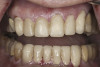

(9.) Preoperative right lateral, closed view.

Figure 9

(10.) Preoperative anterior, closed view. Note the end-to-end occlusion of the anterior teeth and the wear on the incisors and centrals resulting in no anterior or canine guidance.

Figure 10